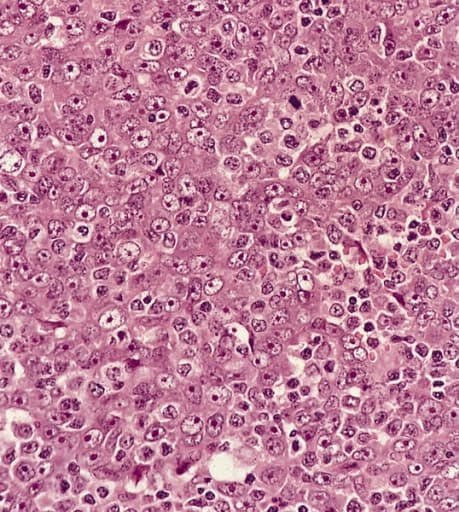

Le carcinome du nasopharynx est un cancer se développant à partir des cellules épithéliales du nasopharynx. Il fait partie des cancers des voies aérodigestives supérieures. Il s'agit du cancer épithélial le plus fréquent chez l'adulte. Cette tumeur peut rester localisée ou s'étendre vers la base du crâne, l'oropharynx, la cavité buccale et le palais. Les métastases sont typiquement des métastases ganglionnaires cervicales. Ces métastases sont souvent le mode de diagnostic de ce cancer. La biopsie donnant le diagnostic. Les autres signes comprennent douleur, trismus, otite, régurgitation nasale par parésie nerveuse, perte de l'audition et paralysie de nerfs crâniens. Plusieurs causes sont identifiées : l'infection à virus d'Epstein-Barr, des facteurs génétiques et des facteurs environnementaux comme les nitrosamines. Le traitement repose sur la radiothérapie, la chimiothérapie et l'utilisation d'interféron. Il s'agit du cancer épithélial le plus fréquent chez l'adulte mais il peut apparaître dès l'enfance, puisqu'au Royaume-Uni l'incidence annuelle varie de 0,3 entre 0 et 14 ans, à 2 cas pour un million d'habitants entre 15 et 19 ans. Certaines populations ont une incidence plus élevée comme en Chine et en Tunisie. Ce cancer est responsable d'un tiers des cancers du rhinopharynx. La première description de ce cancer date de 1921. La détection d'ADN viral du virus d'Epstein-Barr dans le carcinome du nasopharynx des enfants, et particulièrement dans les types 2 et 3, montre que ce virus est un des facteurs dans la carcinogenèse. Mais la carcinogenèse est un processus multifactoriel. Il semble que le taux de l'ADN détectable dans le plasma des malades soit corrélé avec la réponse au traitement et au risque de récidive. Chez les adultes plusieurs autres facteurs sont en cause : facteurs génétiques, alimentation (particulièrement le poisson salé) contenant des nitrosamines volatiles. Les métastases ganglionnaires sont souvent le mode de révélation de ce cancer. La biopsie donnant le diagnostic.